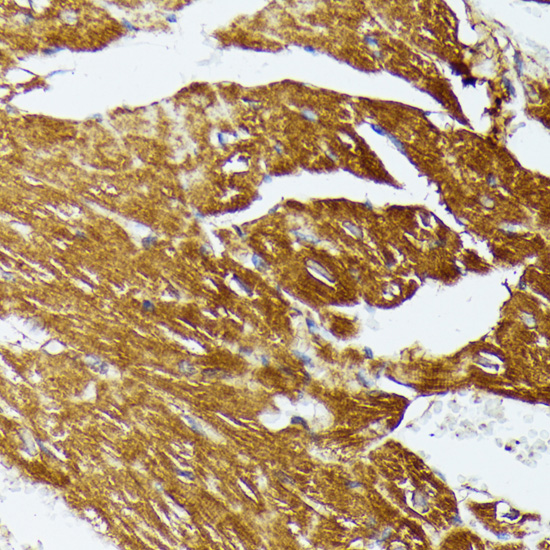

Immunohistochemistry of paraffin-embedded rat heart using COX15 at dilution of 1:100 (40x lens).